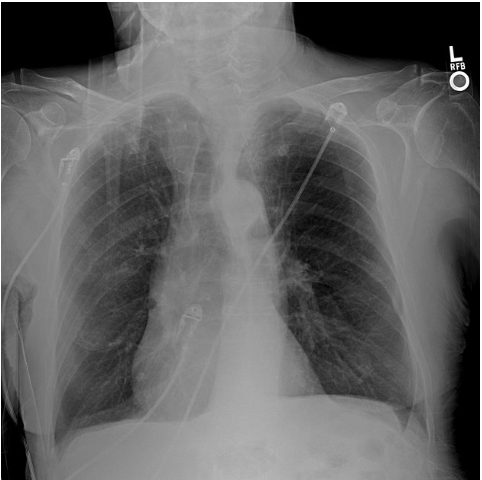

what should an xray of the lungs look like

xray of lungs with COPD

widened intercostal spaces

flattened hemidiaphragms

squared off costophrenic angles and rib angles that approach 90 degree angles

xray of lungs with atelectasis

diaphragm elevation on the collapsed side

deviation of the mediiastinum, trachea (deviated towards collapsed side

increased density of the lobe